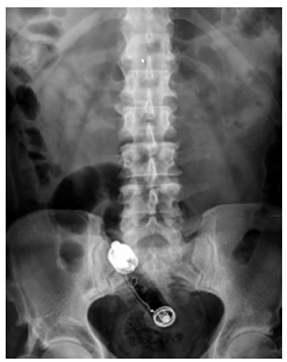

Las radiografías (Rx) de abdomen son los exámenes de primera mano para hacer el abordaje inicial; estas permiten localizar el objeto, estimar el tamaño y determinar la cantidad. Se requiere usar una proyección anteroposterior y otra lateral para dar una localización más exacta (Figuras 3 y 4). Los objetos como el metal o grava son más densos que los tejidos que los rodean y permiten una mejor visualización en las Rx. Los materiales orgánicos que poseen una densidad similar a los tejidos humanos pueden no ser observados en las diferentes proyecciones 9. La no observación de un cuerpo extraño en la Rx no descarta la presencia del mismo.

Según las características del cuerpo extraño, puede usarse la clasificación de fácil agarre, dentro de los que se encuentran elementos cortopunzantes pequeños, huesos, espinas y fálicos como los consoladores, vibradores, velas, vegetales y frutas (Figura 1). Los de difícil agarre corresponden a envases, botellas, tarros, frascos, esferas, bombillos, entre otros (Figura 2).